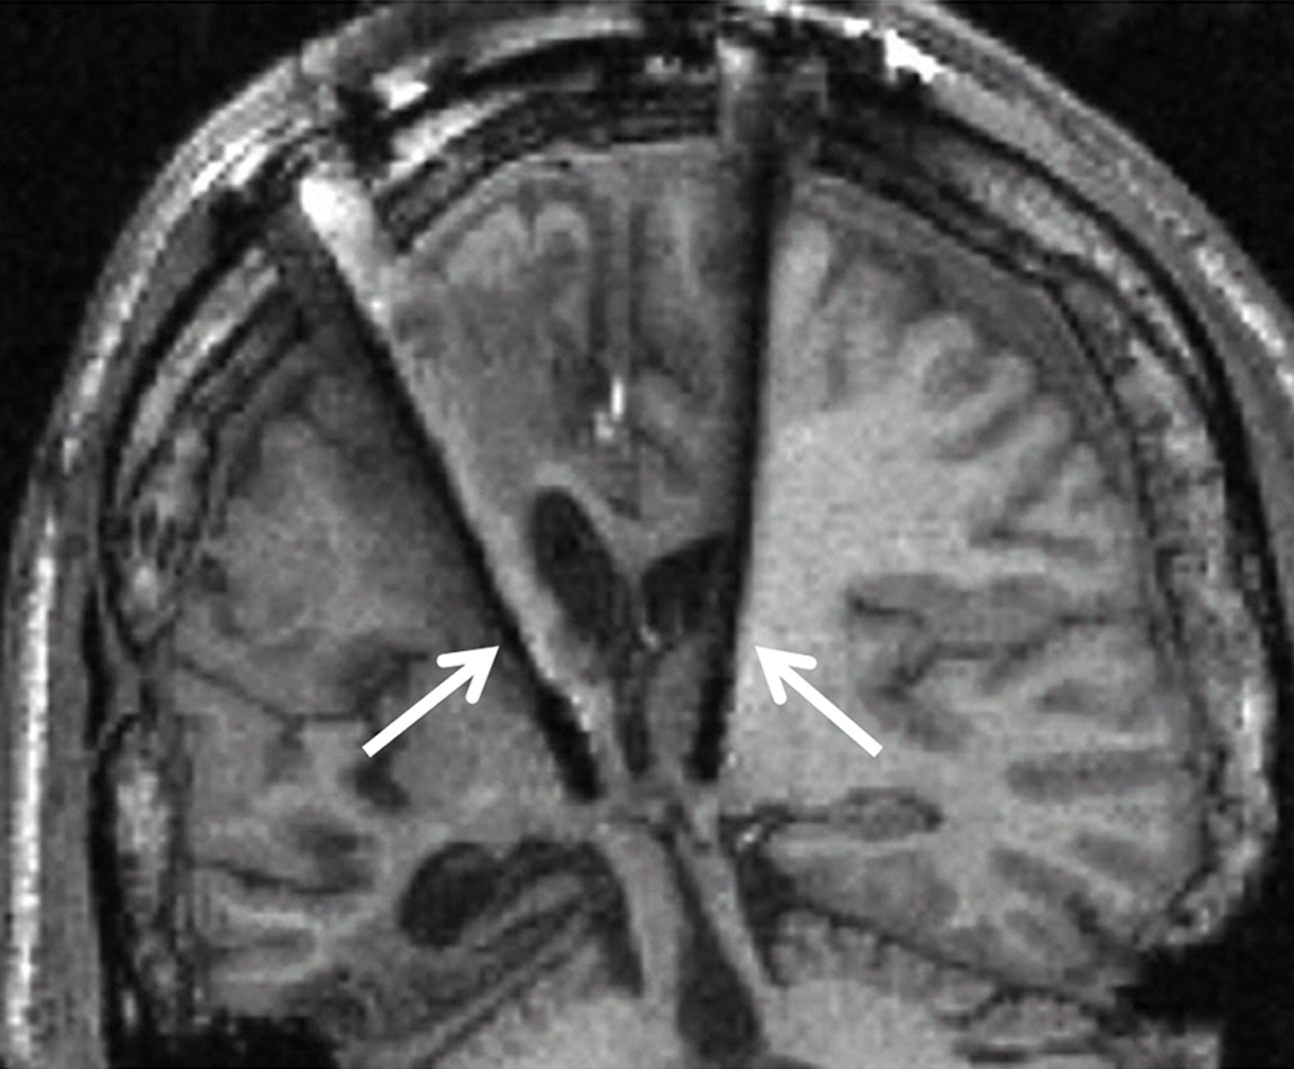

In a more controlled experimental setting, where patients’ selection was based on both their neuropathological status (i.e., specific information about the connections between the central thalamus, cerebral cortex, basal ganglia and other subcortical structures) and behavioral profile (i.e., exhibition of preserved arousal and fluctuating behavioral performance), a 38-year-old patient in a MCS more than 6 years after severe traumatic brain injury was selected for DBS treatment (Schiff et al., 2007). Up to the point of DBS treatment, the patient did not show any clinical amelioration despite a 2-year rehabilitation program. However, after applying DBS in bilateral central intralaminar thalamic nuclei (Figure 2), the patient showed stimulation-related improved levels of arousal, motor control, and interactive behavior as measured by neuropsychological testing during the DBS “on” periods.

Figure 2. Clinical setup of electrodes implementation in the central thalami bilaterally (white arrows) during deep brain stimulation. Adapted from Schiff et al. (2007).

The effects of DBS were attributed to the recruitable large-scale networks underlying the neuropathology of this MCS patient and were interpreted as a promotion of the patient’s arousal regulation via the direct activation of the frontal cortical and basal ganglia systems, innervated by the stimulated thalamic neurons (Schiff et al., 2007; Schiff, 2010).